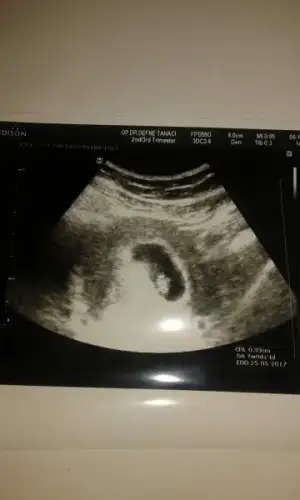

Hazirandaki gebeliğim sonlandı maalesef.pıhtılaşma olmuş ve bebeğimin kalbi durmuş.şimdi allahın izniyle tekrar hamileyim kan suşandırıcı iğne kullanıyyorum.yorum yaparmısınız usg lere.2 side karından .ilk resim 7 hafta 2.si 6+3.

12 KB · Görüntüleme: 113